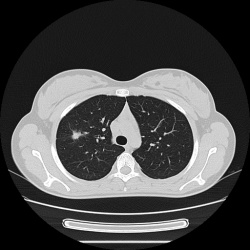

Пациент с диагнозом "пневмония" направлен на рентгеновское исследование ОГК. Какие будут мнения уважаемые коллеги?Контроль после лечения.

Предварительный диагноз "правосторонняя пневмония". Жалуется на выраженную слабость, фебрильную температуру, одышку, кашель с мокротой.

Пациент доставлен ночью скорой помощью в приёмное отделение в довольно тяжелом состоянии. Отмечается повышение температуры до 39 градусов, кашель со скудной мокротой, недомогание, выраженную ...